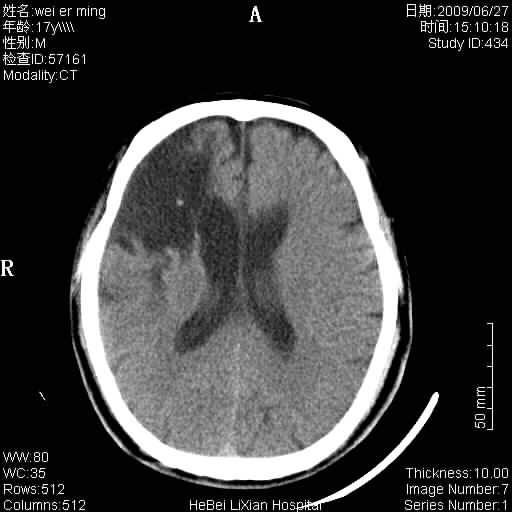

标题: CT20838:帮忙看看,是软化灶吗?

患者,男,67岁.既往有脑血栓病史.若是软化灶里面怎么出现钙化呢?

支持软化灶伴穿通畸形,钙化为胶质增生、机化、钙化。

支持 右侧额叶软化灶伴脑穿通畸形(钙化为胶质增生、机化、钙化)。

考虑脑软化灶伴钙化。不除外软化灶并穿通畸形存在。